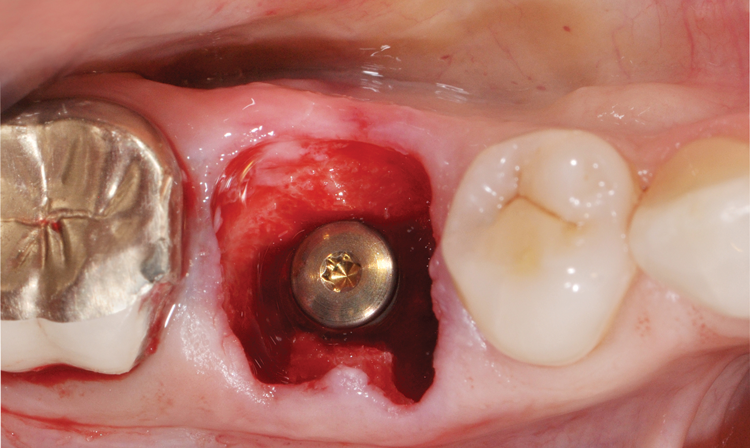

(20.) Immediate implant placement. The residual bone defect, which measures approxi-mately 3 mm, was intentionally developed by planning the use of a suitable implant diameter.

Figure 20